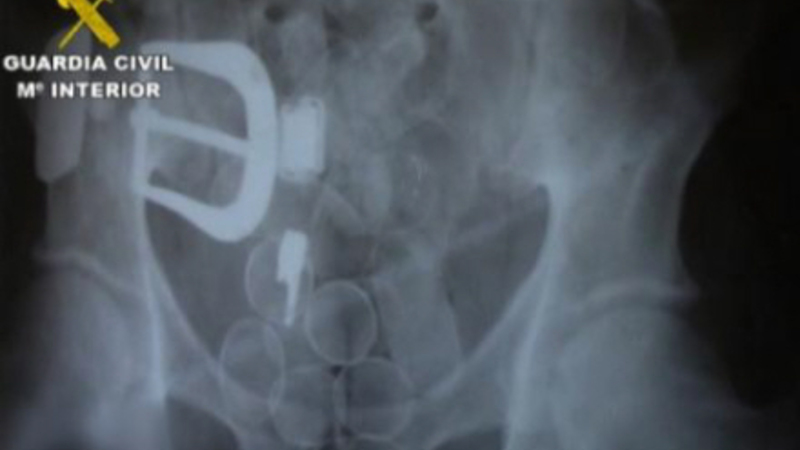

Ifølge rapporten fra Guardia Civil blev offeret, J.A.U.I., en colombiansk advokat med spansk pas, hyret af narkobagmanden fra sit hjemland til at transportere kokain i maven fra Sydamerika til Spanien.

Manden, der havde hårdt brug for penge, tog en lang rejse fra Colombia til Chile, hvor det angiveligt er lettere at slippe igennem kontrollen med narkotika. Herfra rejste J.A.U.I. videre til Spanien.

Lige efter ankomsten til Spanien fik manden forfærdelige mavesmerter og bad sin 'arbejdsgiver', den colombianske narkobagmand J.A.V.H, om at komme på sygehus. Alt tydede på, at der var gået hul på en af pakkerne i hans mave og at han hurtigt blev forgiftet indefra. Han havde akut brug for hjælp.

Men det afviste narkobossen, der var mere bange for at miste narkoen. Han gav i stedet sit muldyr en ordentlig dosis smertestillende medicin for at milde den ulidelige smerte.

Retsmedicinere har efterfølgende slået fast, at manden døde af forgiftning, og fik skåret maven op post mortem. Narkoen var herefter blevet taget ud, og maven var igen blevet syet sammen med fiskesnor.